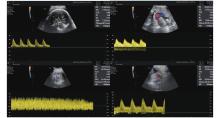

Figure 5

Speckle tracking- Fetal HQ. (A) Marked myocardial region of interest in the left ventricle (LV) and right ventricle (RV); (B) Deformation vectors in the LV and RV; (C) LV and RV global longitudinal strain (GLS) analysis. (Images were acquired on E10 Voluson ultrasound machine and analysed using FetalHQ software)"